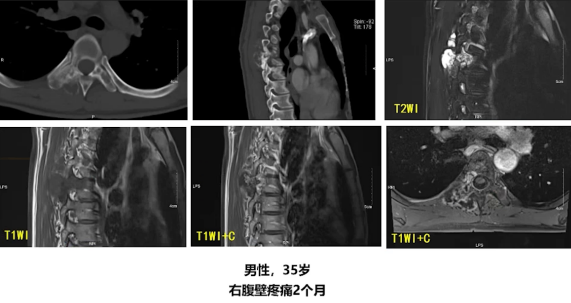

以一例典型的胸椎软骨肉瘤二级为例,胸椎影像显示病变累及椎体及附件,可见骨质破坏。CT显示不规则溶骨性破坏,伴点状钙化及轻度膨胀性骨质改变,整体密度显著不均匀。MRI表现更具特征性,T2像显示等高信号成分呈明显高信号,高信号内见点状低信号提示钙化灶,T1像呈低信号表现。增强扫描显示特征性的分叶状边缘强化,整体呈分叶状强化模式。这种分叶状强化结合钙化灶、T2高信号及轻度骨质膨胀,构成了典型的软骨肉瘤影像特征。